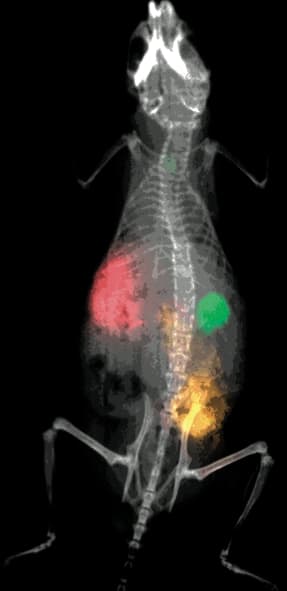

Although the overlay methods are beneficial, repeated imaging of the same animal in different imaging sessions often results in misinterpretation of the signal localization, as animal repositioning is difficult. The white-light reference image may be suitable for localization of large tumor masses, but lacks the anatomical context required for repeatedly localizing smaller signals of interest and/or mapping the molecular signals to bones or other anatomical structures within the animal. Hoping to realize the full potential of the dark-field molecular imaging agents, researchers are beginning to apply multimodal instrumentation that combines dark-field contrast with radiographic anatomical imaging in one system.

To illustrate this move towards multi-modal molecular imaging, Kodak Molecular Imaging Systems (New Haven, CT) has introduced a line of in vivo small-animal imaging systems, including a model that allows the capture of X-ray images. These X-ray images provide the detailed penetrating anatomical guideposts that greatly enhance the localization of the in vivo optical or radioisotopic molecular images. The Kodak Image Station In-vivo F allows for very high-resolution, multi-wavelength fluorescence, luminescence, and radioisotopic imaging in small animals, while the Kodak Image Station In-vivo FX includes all of the capabilities of the In-vivo F and the high-resolution X-ray Imaging Module using a Radiographic (X-ray) Imaging Screen.

As the images of each modality are captured without movement of the animal and with no change in optical focus or zoom, the images can easily be merged or overlaid in software for precise co-registration.

In vivo imaging systems greatly enhance the localization of molecular signals in live animals. These systems are now used by top academic, biotechnology, and pharmaceutical research institutes worldwide. The flexibility of these systems allows the combination and co-registration of multiple wavelengths and multiple modalities of imaging including optical, radioisotopic, and radiographic imaging. Several studies are now in progress that will further detail the utility of combining, co-registering, and performing the appropriate analysis of the multiple imaging modalities.